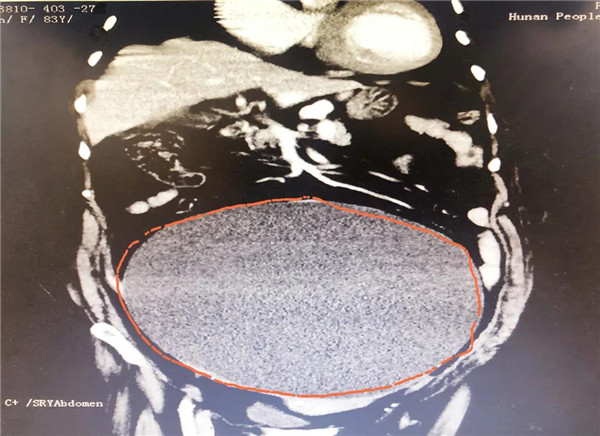

CT显示,巨大的肿瘤几乎占据老人整个盆腔和腹腔。

2021年10月29日,彭娭毑住进湖南省人民医院妇科病房。完善相关检查发现,巨大的肿瘤几乎占据她整个盆腔和腹腔,并且压迫肠道和膀胱,这也是老人尿频的原因。与此同时,术前血液检查发现了异常——全系细胞减少;进一步骨髓穿刺结果为:可疑B细胞淋巴瘤骨髓浸润。